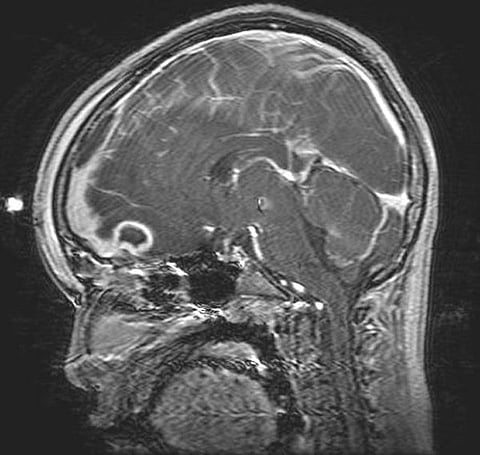

By spreading awareness about the signs, symptoms, world brain tumor day helps in early detection and timely intervention. (Wikimedia Commons)

World Brain Tumor Day shines a spotlight on brain tumors, which are abnormal growths in the brain or surrounding tissues. These tumors can be benign or malignant, and their impact on individuals and their loved ones can be devastating. By promoting awareness about the signs, symptoms, and available treatments, this day plays a crucial role in early detection and timely intervention, leading to improved outcomes for patients.